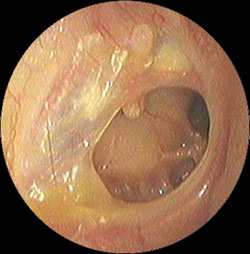

・鼓膜の内側に褐色の液体の貯留を認める

などの症状がでてきます。

・上記の滲出性中耳炎の鼓膜に小さな切開をいれ、内部の液体を吸引し、鼓膜チューブを挿入

・左図の処置後から1週間後、鼓膜内側には液体は溜まっておらず、正常の鼓膜の色である